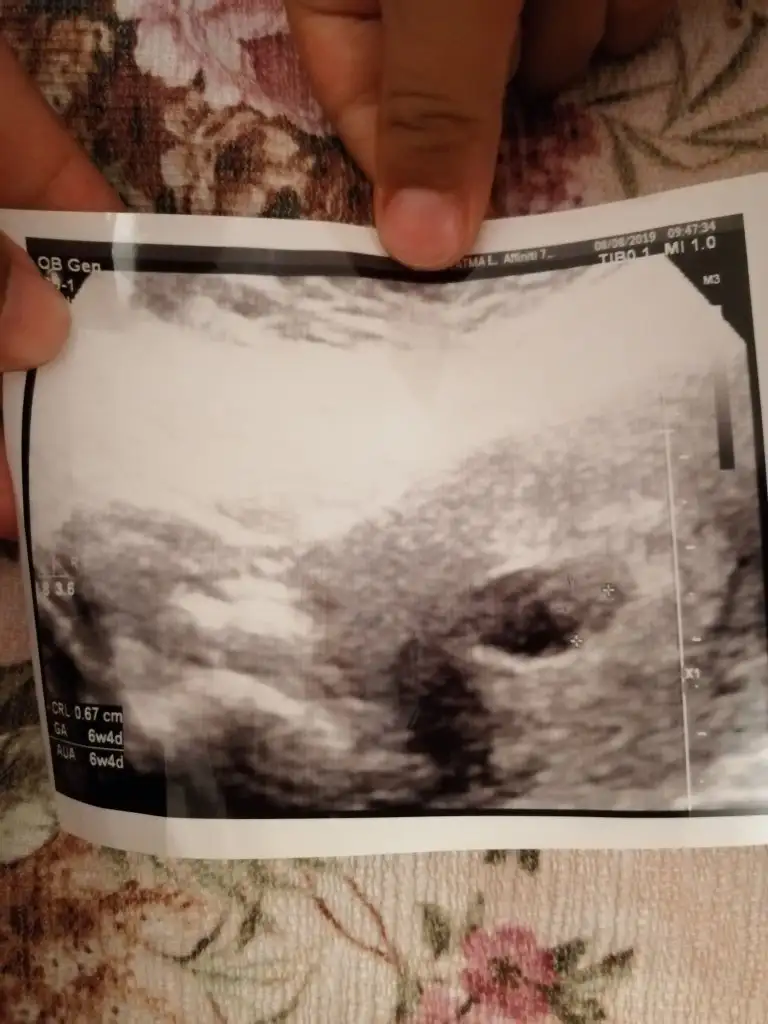

Kizlar 11 haftalik ramzi teorisini göre ne olabilir tahmin yapabilir misiniz

Eklentiler

• 15602436579815690336874001636402.webp

15602436579815690336874001636402.webp

17,3 KB · Görüntüleme: 1.133